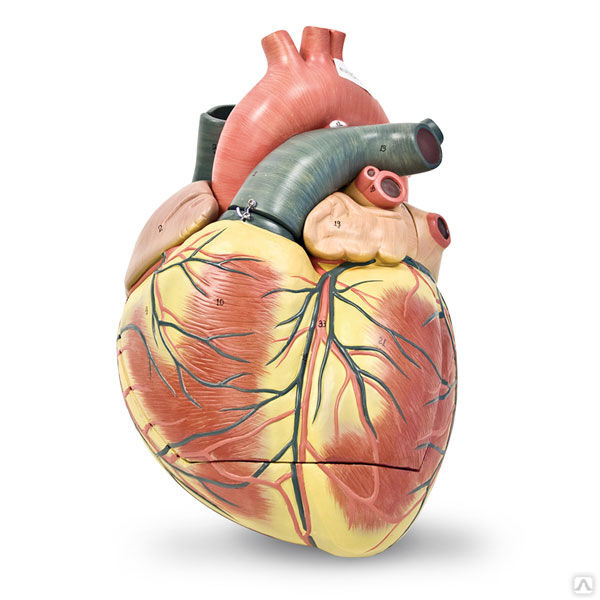

Фотографии и 3D-модели анатомии сердца человека